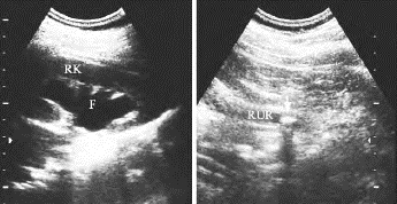

图29-17 输尿管结石声像图

右肾肾盂积水,输尿管上段结石(箭头所示)